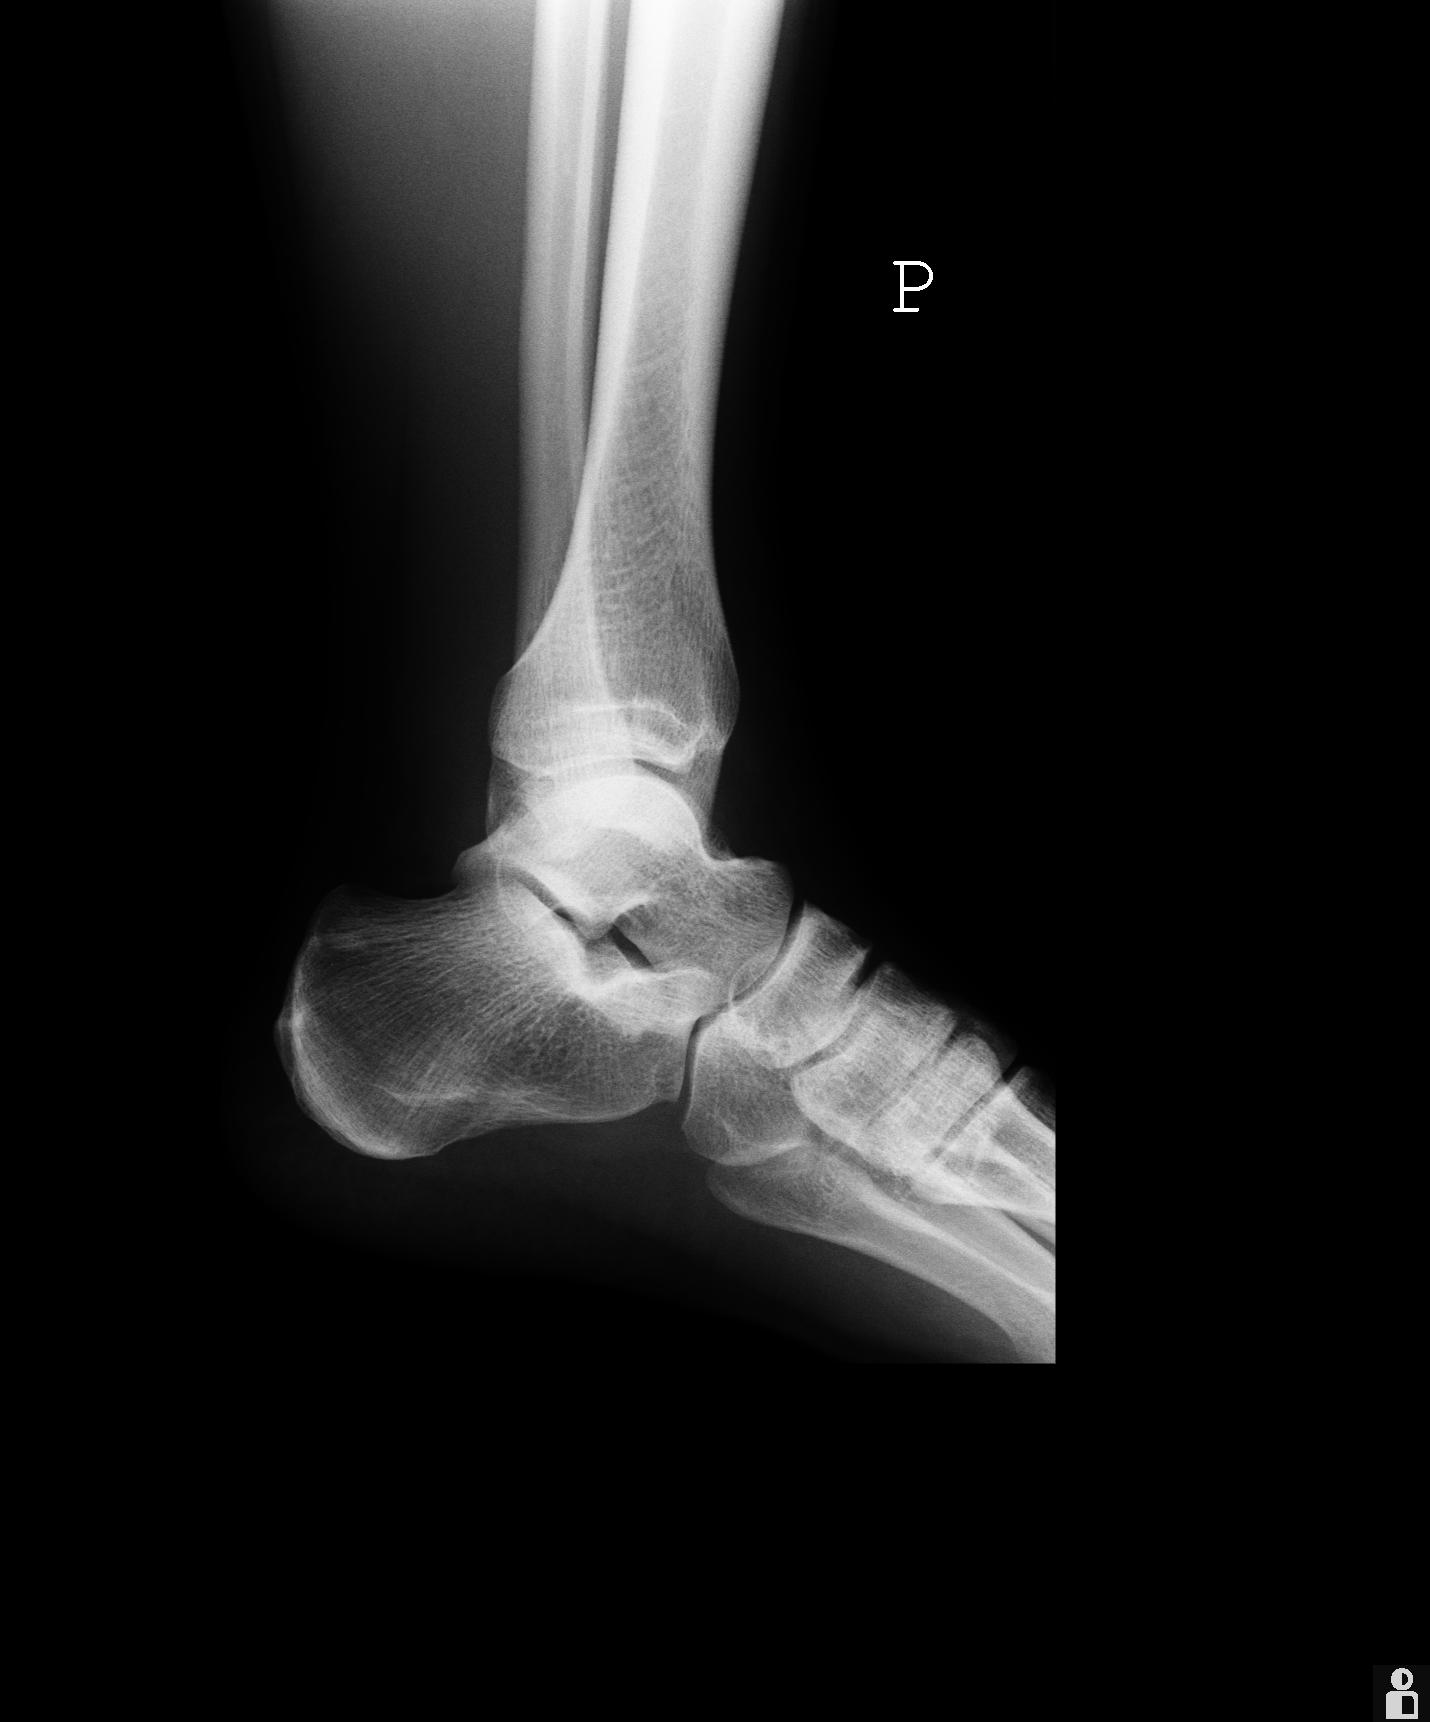

5 tygodni temu doznałem urazu stawu skokowego. Lekarz powiedział, że to nic takiego i po 2 tygodniach będzie dobrze, a ja mam cały czas problem ze stawem. Boli w pewnym zakresie ruchu, jest lekko opuchnięty. Czy ktoś kto ma jakieś pojęcie mógłby zerknąć na zdjęcie RTG?